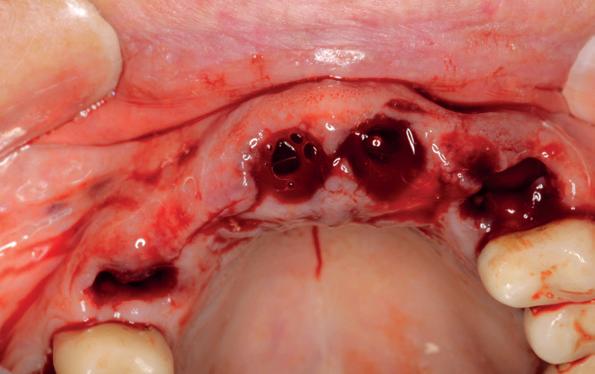

Dit betekent in eerste instantie dat de dentitie invasief wordt gesaneerd wat neerkomt op totaal extractie: een volledige gebitsprothese voor in de boven- en onderkaak. Een implantaat gedragen vaste voorziening kan op termijn aan de wens van de patiënt voldoen. De chirurgische behandeling omhelst het plaatsen van implantaten op geleide van een boormal eventueel in combinatie dan wel separaat uit te voeren botopbouw en bilaterale sinuslift. Zes maanden na de eerste fase wordt het mogelijk de tweede fase uit te voeren, namelijk de abutment chirurgie. De immediaat gebitsprothese dient als (tijdelijke) noodvoorziening en wordt tussentijds aangepast.

Ongeveer drie maanden na de totaal extractie zien wij de patiënt terug voor verder klinisch en röntgenologisch onderzoek en het opstellen van het definitieve implantologische behandelplan. Gebitsmodellen worden gemaakt waarbij de kaakwallen worden gescand ter voorbereiding van de chirurgie. Van groot belang is het vervaardigen van een CBCT-scan om zowel de breedte als de hoogte van de processus te bepalen in de boven- en onderkaak. Daarnaast is het van belang de sinusbodem goed in kaart te brengen en eventuele septa in beeld te brengen. Ook in de onderkaak is het noodzakelijk te achterhalen hoe de canalis mandibularis loopt en waar precies het foramen mentale zich bevindt. Bij patiënt G. wordt al snel duidelijk dat de kaakbreedte in zowel de onder- als de bovenkaak vrij smal verloopt. Een botopbouw kan daarom niet voorkomen worden en bij de voorbereiding van het plaatsen van de implantaten zal daarom ook de botopbouw per kaak opgenomen moeten worden in het behandelplan. Een laterale botopbouw met een sinuslift in het eerste kwadrant is vrijwel onvermijdelijk.

5. Implantaten geplaatst op geleide van een boorsjabloon; botopbouw met sinuslift volgens de GBR-techniek en Caldwell Luc methode; materialen: Oragraft & BioOss, Ossix membr, hyaluronzuur. In de BK is gekozen voor Bego implantaten (Bego SC en RSX 3,75x 11,5 & 13mm).

6. In het front zijn Bego 3,25mm

Tijdens de chirurgische behandeling worden na het afschuiven van de flap de posities bepaald van de implantaten met de boorsjabloon. In de bovenkaak worden 7 implantaten geplaatst en in de onderkaak 8

implantaten geplaatst terwijl in de zijdelingse delen voor een bredere diameter (3,75 & 4,1) is gekozen, met lengte 8,5 en 10mm.

7. OPT na abutmentchirurgie 6 maanden later. De integratie van de implantaten met de botopbouw & sinusliften verloopt voorspoedig.

Lateraal van de implantaten wordt de kaak fors uitgebouwd volgens de Hybride GBR-techniek met Oragraft (allograft) van Lifenet die wordt vermengd tot een cocktail met BioOss (xenograft) van Geistlich, autoloog geoogste botsnippers en verzameld bloed uit het wondgebied. De botgraft wordt bedekt met een Ossix (crossed linked) membraan en met Hyadent (hyaluronzuur) overspoten. De sinuslift wordt gelijktijdig met de laterale botopbouw volgens de Caldwell Luc methode uitgevoerd en de uitgeprepareerde holte opgevuld met de botgraft. De flaps worden eerst horizontaal ontlast (gemobiliseerd) en vervolgens naar elkaar toe gehecht met vicryl rapide. Daarbij wordt gebruikgemaakt van horizontale matrassen, zodat de wondranden passief tegen elkaar